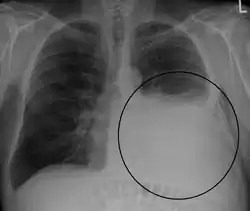

A pleural effusion appears as an area of whiteness on a standard posteroanterior chest X-ray.[15] Normally, the space between the visceral pleura and the parietal pleura cannot be seen. A pleural effusion infiltrates the space between these layers. Because the pleural effusion has a density similar to water, it can be seen on radiographs. Since the effusion has greater density than the rest of the lung, it gravitates towards the lower portions of the pleural cavity. The pleural effusion behaves according to basic fluid dynamics, conforming to the shape of pleural space, which is determined by the lung and chest wall. If the pleural space contains both air and fluid, then an air-fluid level that is horizontal will be present, instead of conforming to the lung space.[16] Chest radiographs in the lateral decubitus position (with the patient lying on the side of the pleural effusion) are more sensitive and can detect as little as 50 mL of fluid. Between 250 and 600mL of fluid must be present before upright chest X-rays can detect a pleural effusion (e.g., blunted costophrenic angles).[17]

Chest computed tomography is more accurate for diagnosis and may be obtained to better characterize the presence, size, and characteristics of a pleural effusion. Lung ultrasound, nearly as accurate as CT and more accurate than chest X-ray, is increasingly being used at the point of care to diagnose pleural effusions, with the advantage that it is a safe, dynamic, and repeatable imaging modality.[18] To increase diagnostic accuracy of detection of pleural effusion sonographically, markers such as boomerang and VIP signs can be utilized.[19]

Massive pleural effusion, later proven to be hemothorax in a South Indian male.